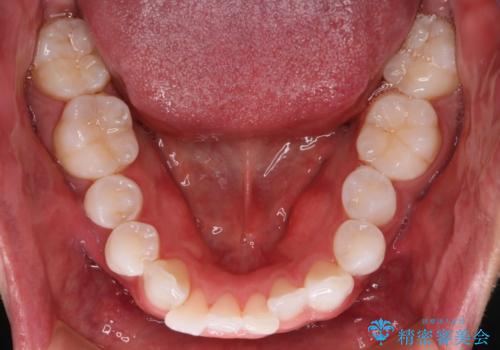

治療症例の内容

- 患者様

- 20代男性

- 矯正装置

- インビザライン

- 治療計画

- がたつきが気になるとの事で来院されました。

目立たない装置で費用も抑えたいとの希望があったため、インビザラインにて治療をすることとなりました。

上下顎ともにIPR(歯と歯の間を削る処置)を行い歯並びを整える治療計画を立てました。